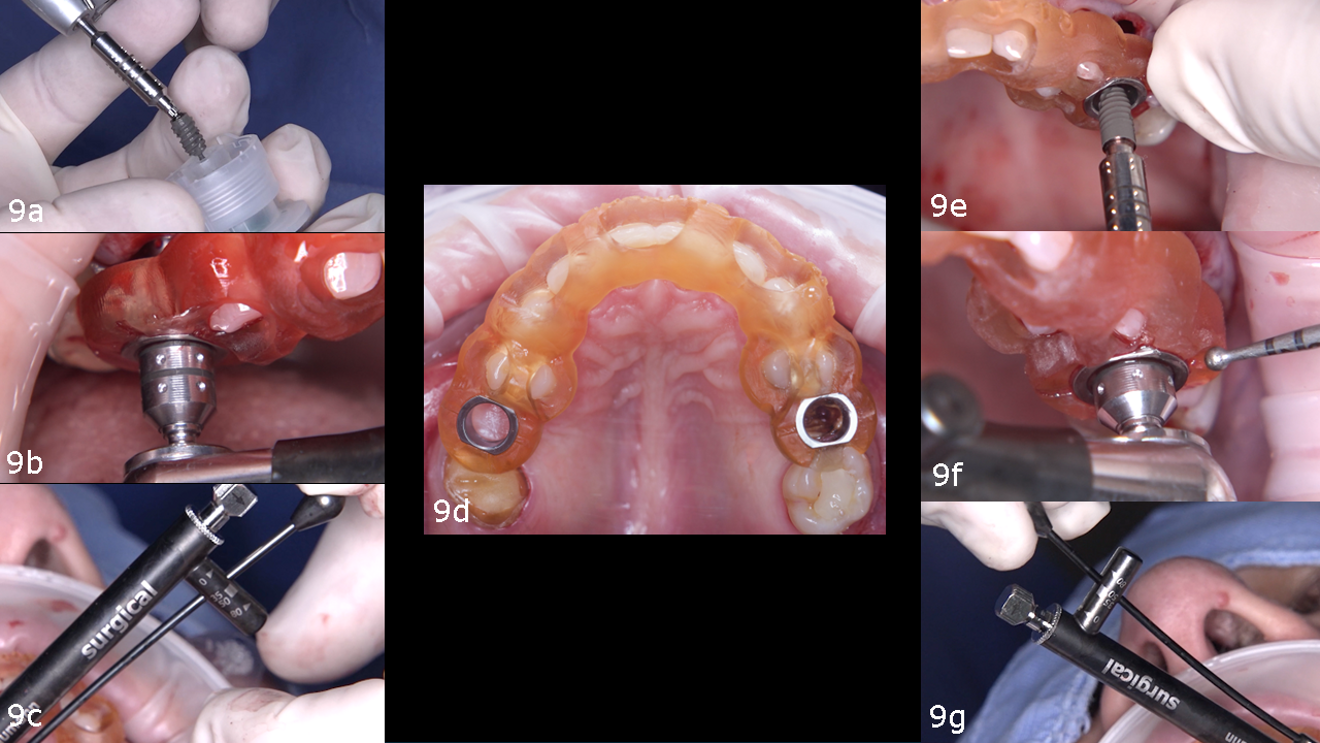

The surgical guide was inserted and verified for accurate fit. Osteotomy preparation was carried out according to the protocol generated by coDiagnostiX (Dental Wings), tailored to the planned implant types on each side (Figs. 8a–g). The Straumann BLX implant was placed into site #15, achieving primary stability at 30 N cm. The Straumann BLC implant was inserted into site #25, reaching primary stability at 50 N cm (Figs. 9a–g).